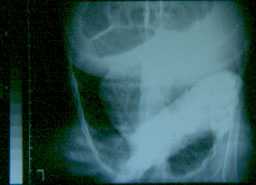

RX: addensamento antro-basale dx. Ha una anemia consistente (Hb 7,2), una iperleucosictosi neutrofila (WBC 62.OOO GB, N 75% ); una piastrinosi (Pl 770.00O); VES 78, PCR 32 mg/dl; Fe 8 mcg/dl.

La TAC mostra un consolidamento interessante il lobo medio e inferiore dx, con aree di colliquazione, impegno dei linfonodi ilari, voluminoso, confluente e disomogeneo per la presenza di aree necrotiche.